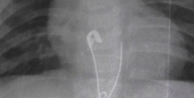

Oruç tuttuğumuzda, normalde vücudumuzun sindirim için harcadığı enerji, sindirim sistemi hiç atık üretmediği için, “hastalıkları” sindirdiğini dile getiren Dr.Ateşsaçan, “Oruç tutarken, hipofiz bezinden büyüme hormonu salgılanır ve tüm vücuttaki hasarlı dokuları onarır, tüm sistemler yenilenir. Canlılık artar ve yaşam uzar. Öncelikle organlarımız gözden geçirelim ve neler yenilmeli hatırlayalım: Karaciğer :Vücudun geri dönüşüm merkezi gibi çalışır. Karaciğer tüm toksinleri seçip ayırır ve atılmasından sorumlu organa gönderir. Enginarda güçlü bir antioksidan olan “silymarin” var.

Silymarin zarar görmüş karaciğer dokusunun tekrar yapılandırılması için önemlidir. İftar da 1 adet enginar karaciğeri temizler Gün içinde kullanılacak 1 tatlı kaşığı toz zerdeçal karaciğeri temizler. Etken maddesi kurkumindir. Kara ciğeri kuvvetlendirir, karaciğer hasarına karşı önleyici etki gösterdiği saptanmıştır. Ağır yağlı yemekler, şekerli ve tatlı gıdalar, katkılı ve ambalajlı ürünler karaciğeri yorar” dedi.